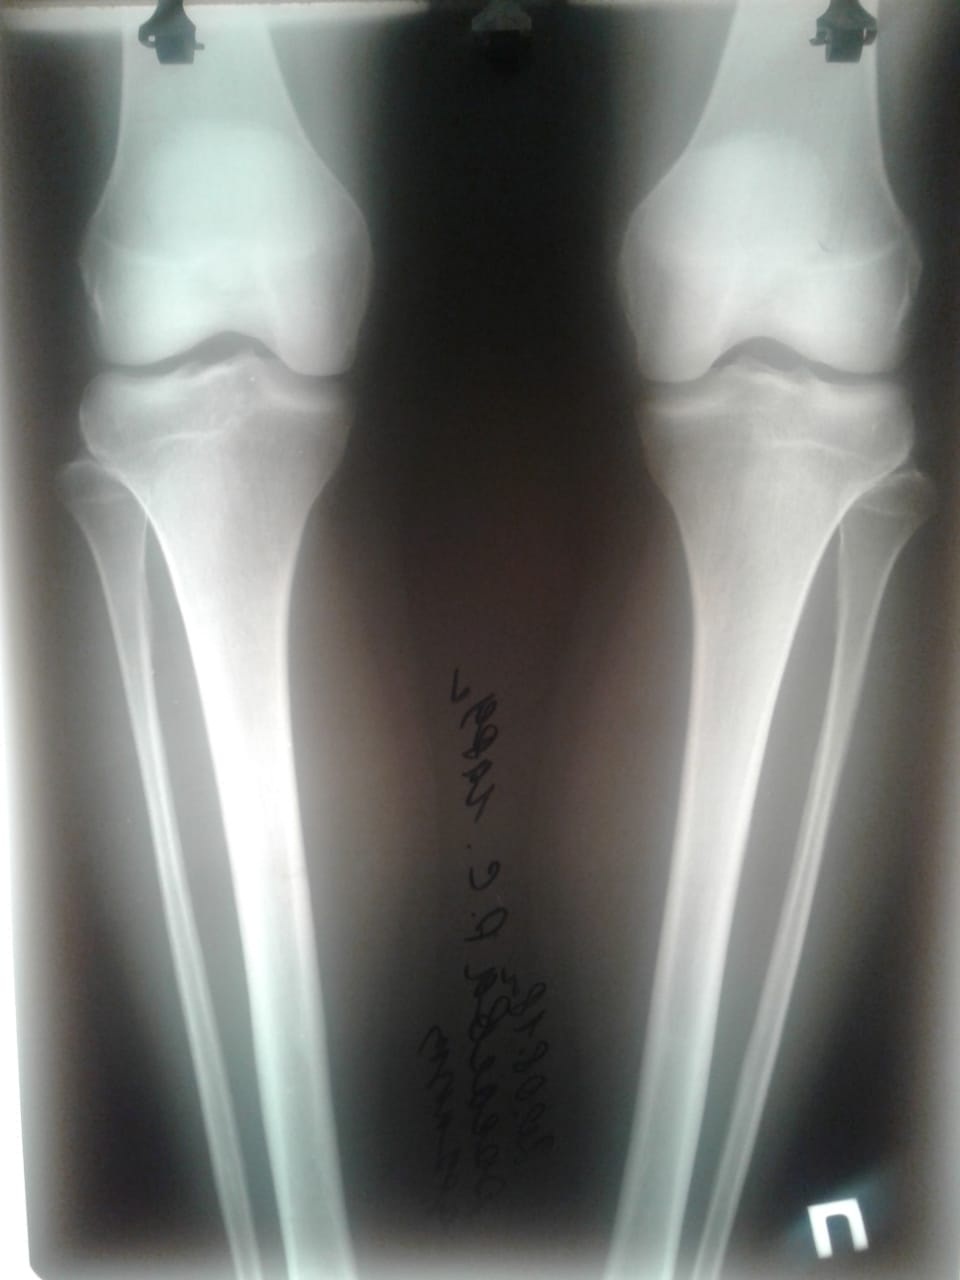

Исходник - 29 лет.

Дата операции - 23.08.2018г.

Ротация справа.

Дата снятия аппаратов-29.11.2018г.

Срок сращения- 95 дней.